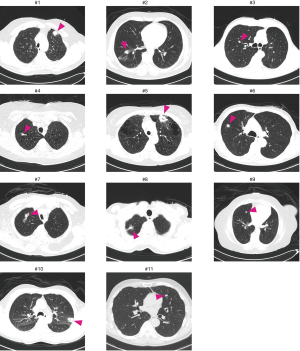

A total of eleven patients were enrolled between October 2013 and August 2017. The original target was 20 patients over 2 years; slow accrual prompted the decision to close the study before reaching this sample size goal. The patient characteristics and lesion information are summarized in Table 1. The details of each patient and diagnostic outcomes are listed in Table 2. There were seven male and four female patients with a median age of 67 years (range, 57–90 years). The mean size of pulmonary nodules on CT was 2.1 cm (median, 2.0 cm; range, 1.0–4.4 cm). Nine pulmonary nodules (82%) had a positive CT bronchus sign. Seven pulmonary nodules (64%) were located in the peripheral third lung field. The mean pleural surface-to-pulmonary nodule distance was 1.9 cm (median, 1.9cm; range, 0-5.3 cm). Representative CT images of the pulmonary nodules are shown in Figure 2. Seven cases underwent conventional bronchoscopy as the first procedure. Biopsy tools used for each case are shown in Table S1. Ten out of eleven patients underwent surgery for diagnosis and treatment. One patient (case #4) was surveilled by imaging alone, with a total of three CT scans over two years; the nodule was clinically diagnosed as benign due to diminishing size.